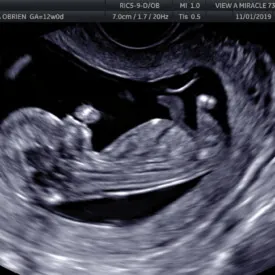

b) Ultrasound NT (Nuchal Translucency)

Teknik : Ultrasound dilakukan dengan menggunakan probe biasa yang dilalukan ke atas bahagian kulit abdomen bagi mengukur saiz janin dan mengukur ketebalan bahagian belakang leher janin.

Jenis ultrasound : 2D hitam putih

Usia kandungan : 11-13minggu

Tujuan pemeriksaan : Untuk mengesan awal risiko Sindrom Down pada janin.